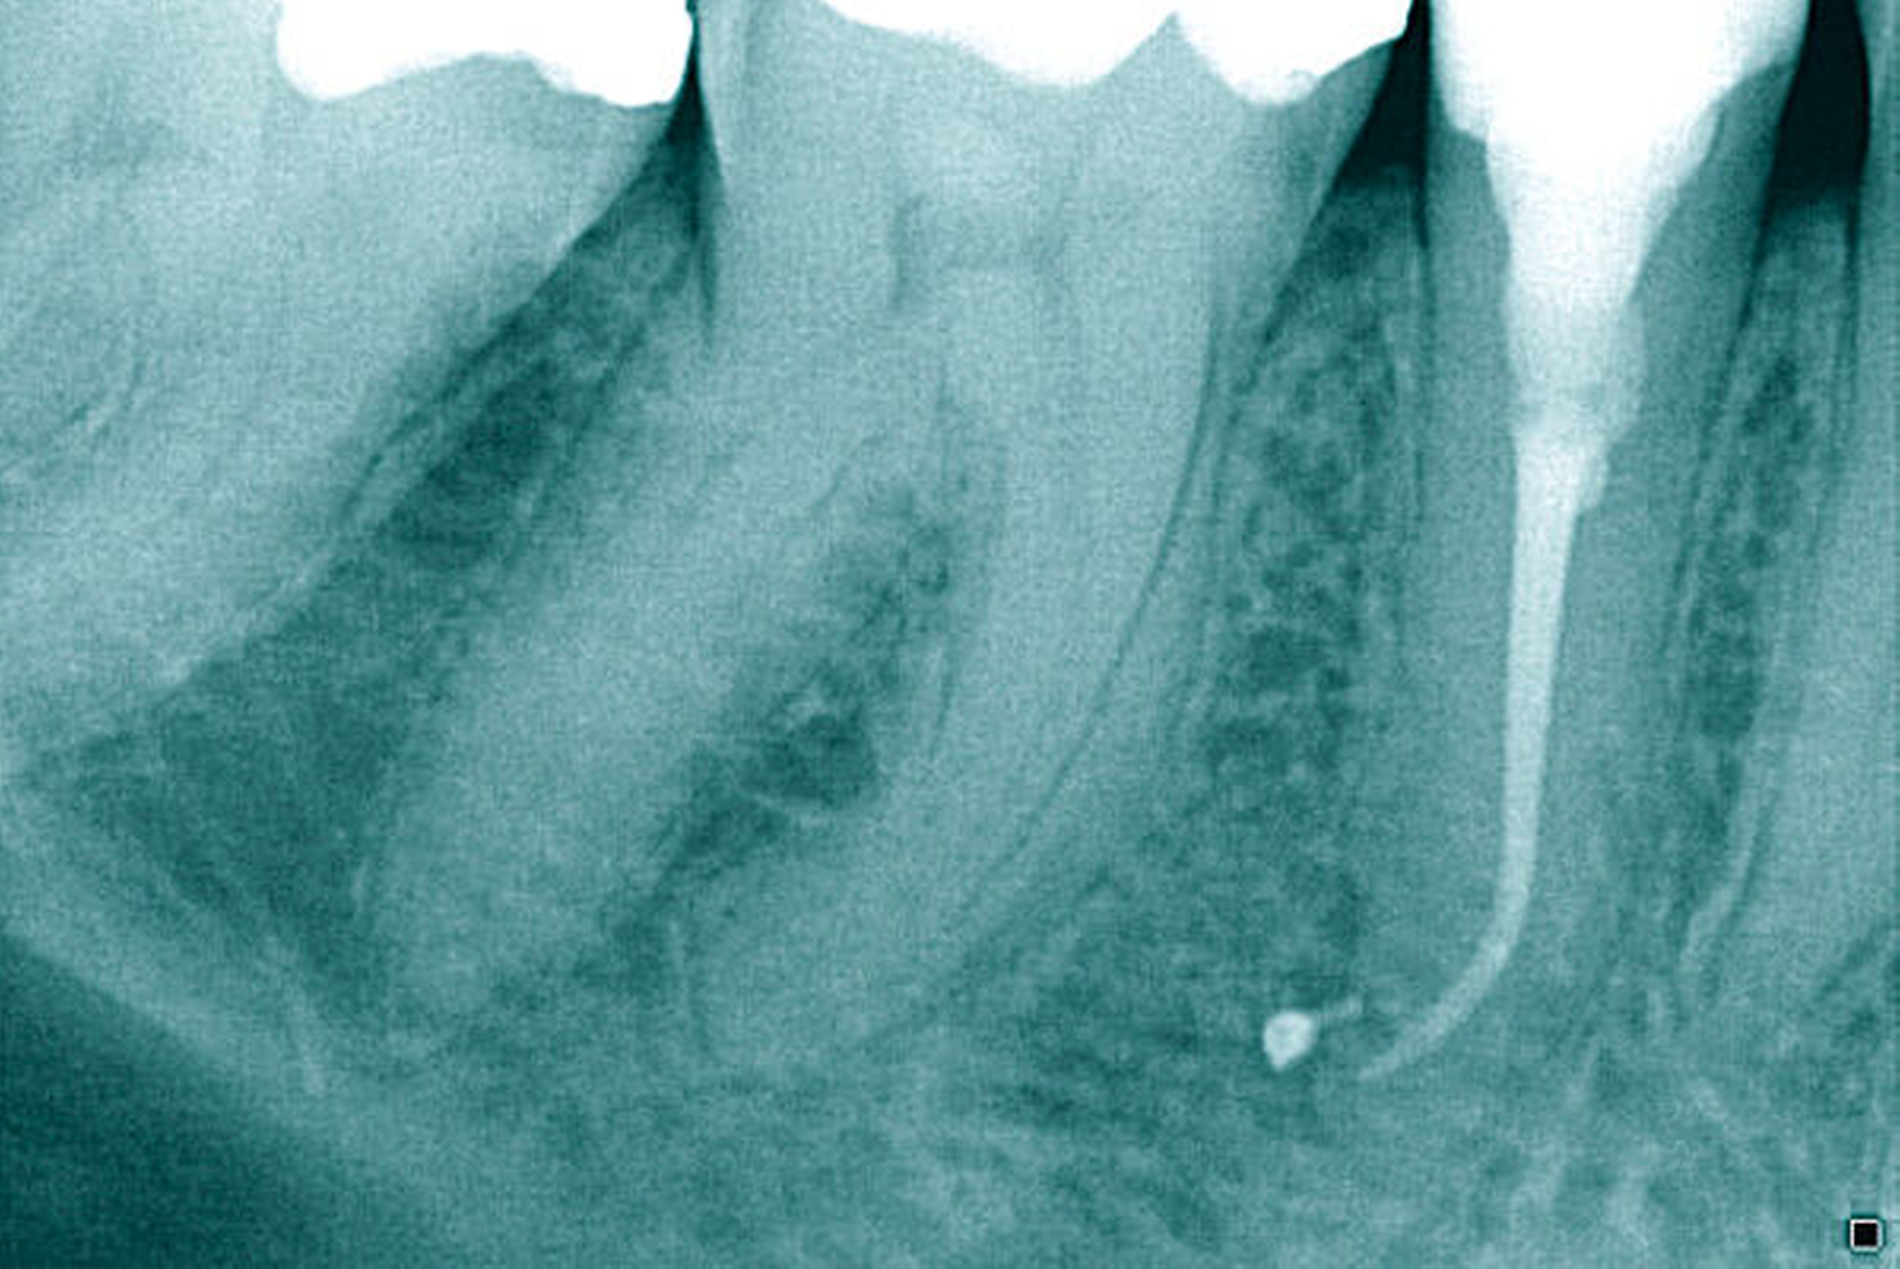

Röntgenbilder können genutzt werden, den anatomischen Schwierigkeitsgrad zu ermitteln. Lässt sich ein Wurzelkanal vollständig bis zum Apex mit einem Krümmungswinkel bis zu 30 Grad und einem großen gleichmäßigen Krümmungsradius erkennen, ist keine erhöhte Schwierigkeit in der Therapie zu erwarten (Abbildungen 1 und 2).

Krümmungsradius: Ist demgegenüber der Verlauf des Wurzelkanals unterbrochen, kann meist mit einer tiefen Wurzelkanalaufteilung gerechnet werden (Abbildung 3) [Reuver, 2002].